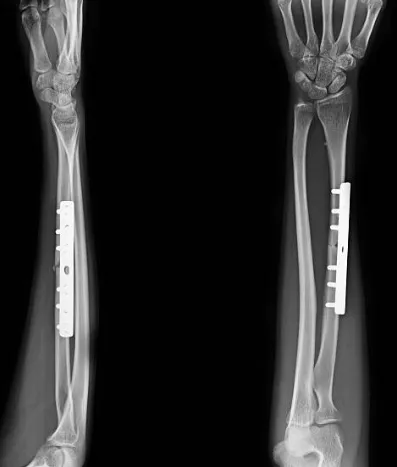

開放性復位內固定手術:在麻醉下,切開皮膚,通過手術器械將骨頭復位並使用螺釘、鋼板、釘子等固定器材將骨頭固定在正確的位置。

關節鏡下手術:通過小切口和關節鏡器械將骨頭復位,並使用細小的固定器材進行內固定,優點是創傷小、恢復快。

開放性復位外固定手術:使用鋼釘或針對骨骼的外固定器件,將骨頭復位並固定。